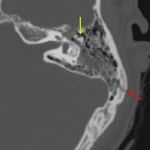

- Acute mixed transverse/longitudinal otic capsule sparing left temporal bone fracture with fracture components extending anteriorly into the temporomandibular joint and superiorly into the lambdoid suture

- Disruption of the left malleoincudal joint

- Partial opacification of the left external auditory canal, middle ear, and mastoid air cells

- Otic capsule sparing temporal bone fracture with ossicular disruption

Acute mixed transverse/longitudinal otic capsule sparing left temporal bone fracture with fracture components extending anteriorly into the temporomandibular joint and superiorly into the lambdoid suture. Associated disruption of the left malleoincudal joint. The left TMJ is located. No sutural diastasis.

Partial opacification of the left external auditory canal, middle ear, and mastoid air cells.